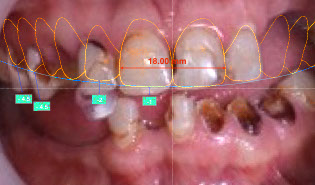

iii) Photo and video capture of smile and face still,

in motion and with emotion

Step 2 – Photo/Video and clinical analysis and design

Brener Clinic takes a series of high-quality digital photos and videos to analyse thoroughly your facial and oral proportions and movement. This data helps us determine the relationship between your smile line, teeth, gums and lips, and how they move together with your individual personality. This analysis allows us to digitally design your smile using DSD technology and plan the treatment.

iv) Clinical analysis and digital design of new smile